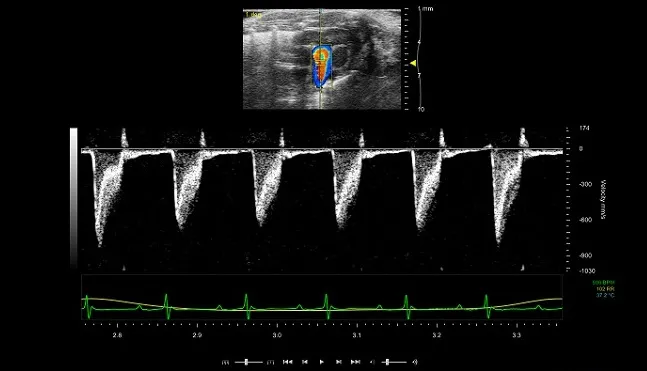

• Colour and power Doppler imaging enabling the visualisation of blood flow within vessels (Figure 2)

Figure 2: Spectral Doppler (bottom) and colour Doppler showing measurement of blood flow in adult mouse pulmonary artery.